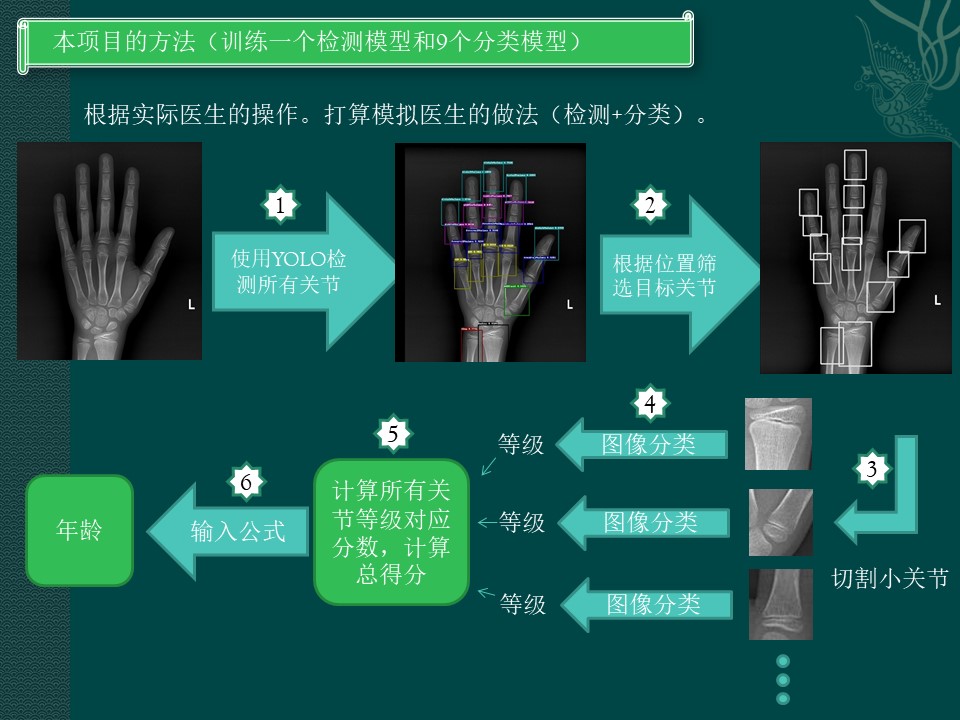

本项目的方法

正是模仿放射医生做骨龄方法。一个个关节找出,分出等级,算总分。